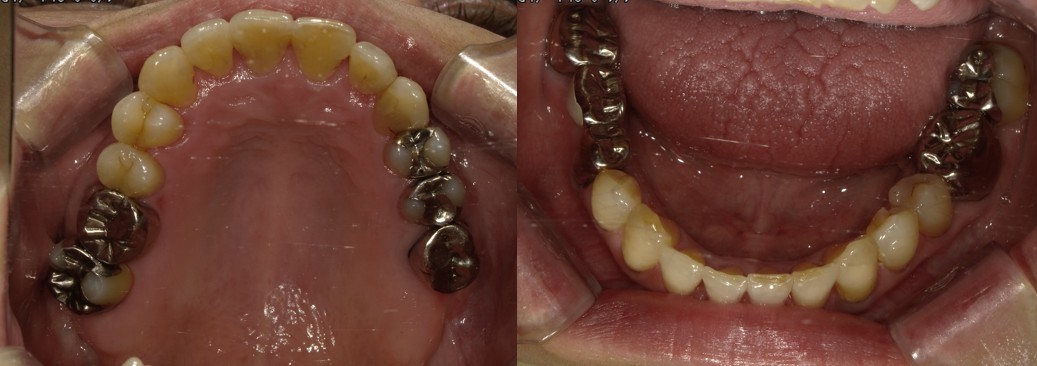

上下のガチャ歯を改善した1症例

治療前 ![]() |

上の歯と下の歯が前後しているのが気になる |

骨格 軽度Ⅲ級 |

今回は即切歯が交叉咬合の一症例です。 |